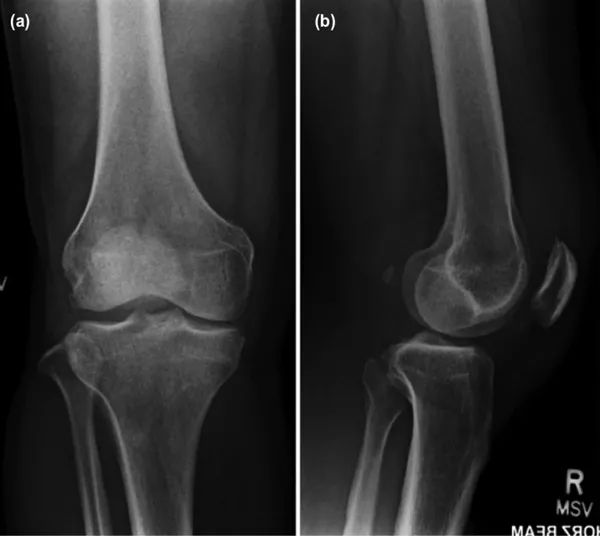

右膝X线检查显示退行性改变,并伴有内侧间室轻度狭窄(图1),关节内未见钙化。

图1 右膝关节X线检查